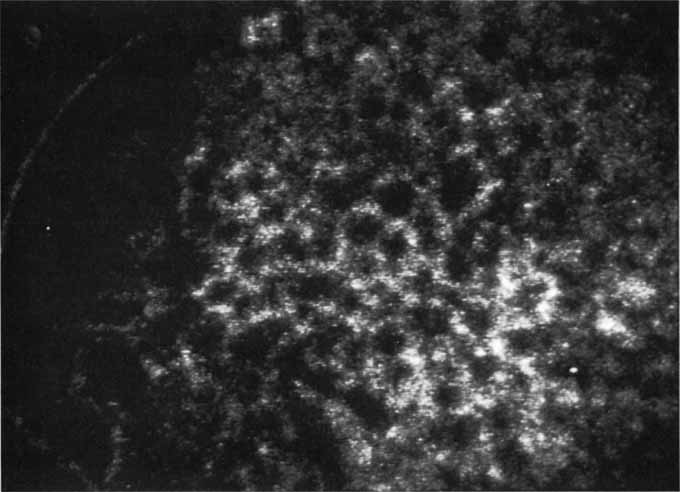

Most promising in this category of inflammatory choroidopathies is a better detection and understanding of the lesions of multifocal choroiditis. Multiple large, scattered, hypofluorescent spots are seen on ICG angiography, particularly in the later phases of the angiogram69 (Fig. 18). These lesions are not evident either on clinical examination or on fluorescein angiography. In addition to having these larger hypofluorescent lesions, patients with multifocal choroiditis have smaller dot-like lesions and hyperfluorescent foci that do not correlate with lesions seen clinically or by FA. They involve the posterior pole and in some patients extend into the mid-periphery. There is also a “papillotropic” involvement, with confluent hypofluorescent lesions surrounding the optic nerve,69 which may be useful in understanding the associated blind-spot enlargement evident in this condition.70 Other zonal visual field defects have been associated with this condition,70 and corresponding ICG abnormalities have been documented in some patients.69

Fig. 18 A. Clinical photograph of a patient with active inflammation associated with multifocal choroiditis. An atrophic scar from previous laser photocoagulation treatment is noted in the temporal macula. The patient reported visual disturbance, and an enlarged blind spot was noted on visual field testing. B. Late-phase indocyanine green study demonstrating a multitude of hypofluorescent spots that were larger than those seen with multiple evanescent white dot syndrome and more numerous and more extensively distributed than appreciated on clinical examination. Note that there is marked confluence of these lesions around the optic nerve, which may help to explain the enlarged blind spot noted on visual field testing.

Natural history data indicate that with progressive increase in vitritis and associated choroidal inflammation, an increase in the number and extent of these hypofluorescent lesions can be documented.40 Furthermore, use of oral steroid therapy as a means of controlling this inflammatory process has been documented to produce not only clinical resolution of the inflammatory process but also corresponding resolution of the hypofluorescent lesions seen on ICG angiography.69 These clearly demonstrated lesions not only may lead to a better understanding of the process of inflammation involved in multifocal choroiditis and potential management strategies but also may serve to differentiate this condition from the ocular histoplasmosis syndrome.